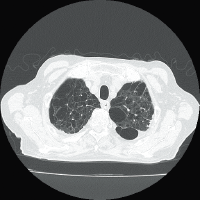

Supria 32 рассчитан на сканирование всего тела с реконструкцией 32 срезов по данным, собранным за 1 оборот.

Для снижения лучевой нагрузки и повышения качества визуализации в КТ SUPRIA используются алгоритм интеллектуального перераспределения дозы IntelliEC и современный метод итерации IntelliIP, позволяющие провести сканирование с очень низкими значениями доз и получить изображения необходимого диагностического качества. В результате лучевая нагрузка на исследуемую область существенно снижается при сохранении высокого качества визуализации, особенно на уровне плотных паренхиматозных органов.